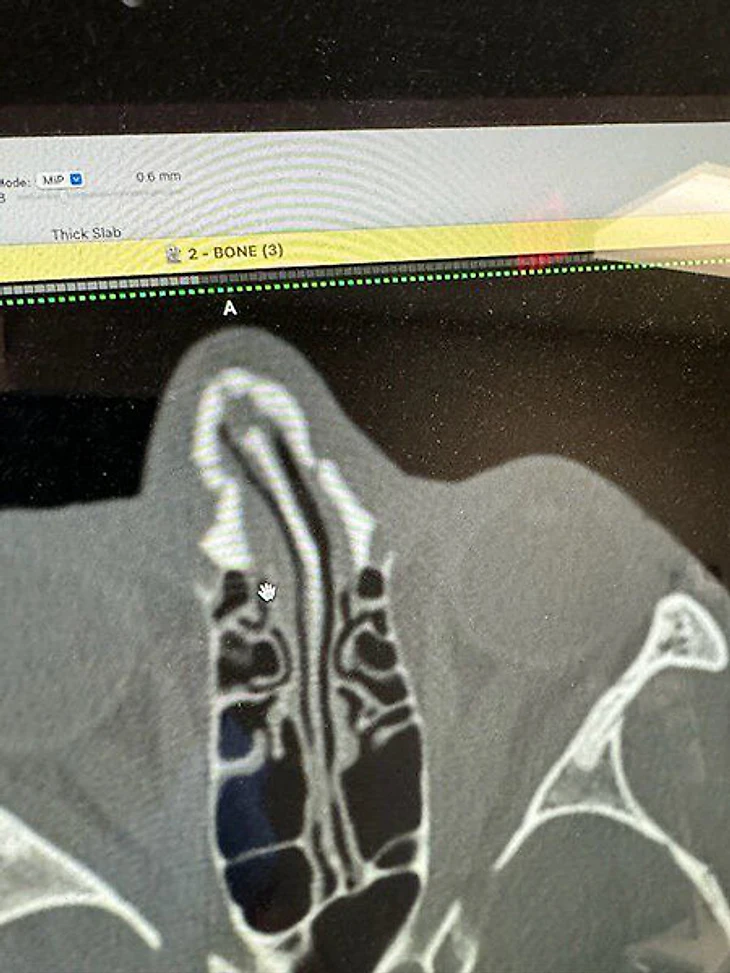

Уже после обследования Порье показал снимок и добавил: «Колено прилетело мне в лицо. До этого был удар головой. Случайно, но больно».

Посмотрите, как сурово выглядят последствия: